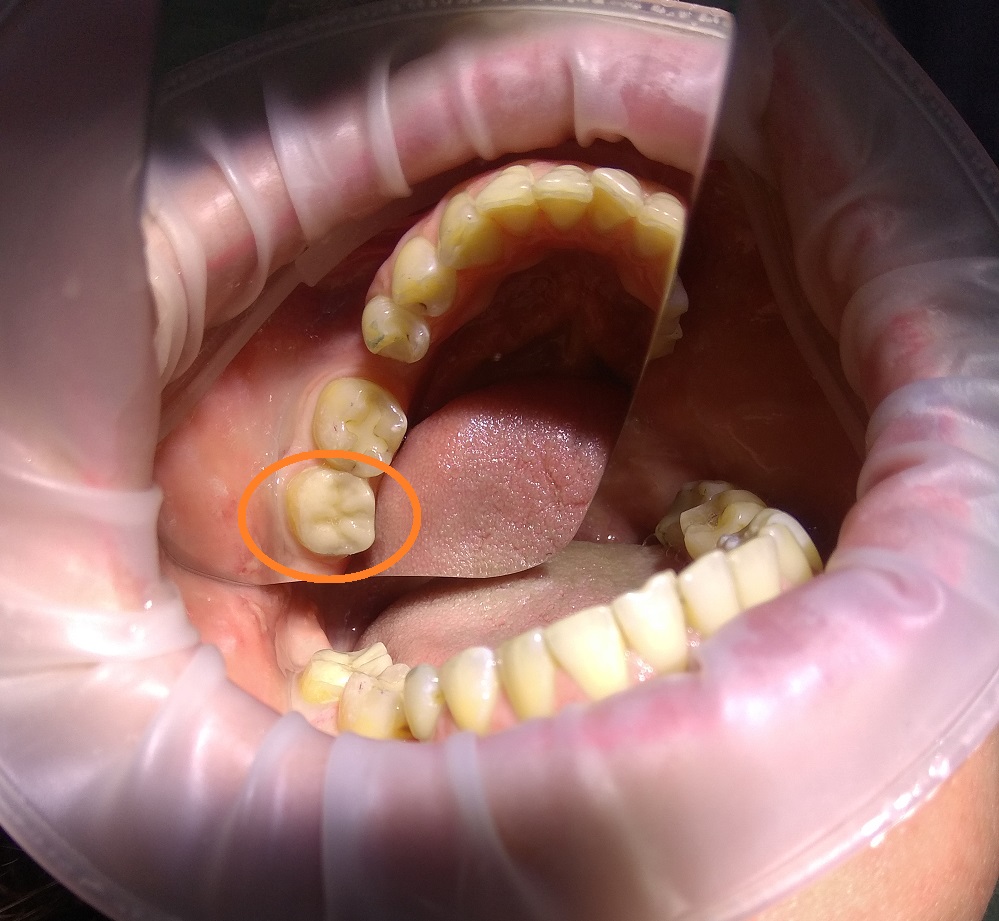

Пломбировочные материалы (пломбы) не обладают вышеперечисленными достоинствами. Уже в течение года пломба темнеет, даёт усадку, часто возникает кариес на стыке пломба-ткани зуба, не восстанавливает в полном объёме анатомическую форму зуба, не даёт точности по окклюзии.

В своей стоматологической практике я активно применяю керамические вкладки (накладки, пломбы) настоятельно рекомендую своим пациентам использовать данный вид лечения вместо обычных пломб. По вопросам установки керамических вкладок записывайтесь ко мне на личный приём.